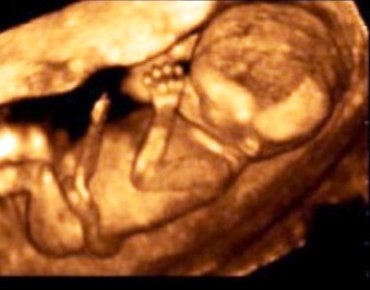

Belelusul este in plin proces de organogeneza si creste. Tu esti plina de emotii si stralucesti! Celulele specializate produc nu mai putin de 250.000 de neuroni pe minut!...

Partea cea mai critica a dezvoltarii copilului a fost depasita, iar embrionul este denumit acum, din punct de vedere medical, fat. aptamana marcheaza si momentul in care...